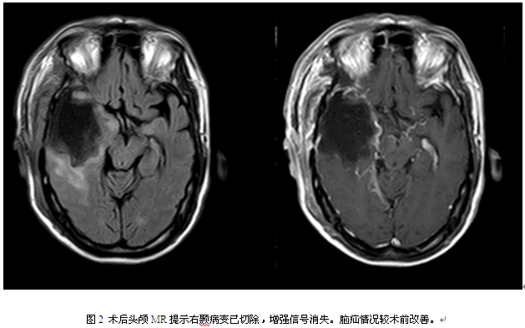

术后病理提示:过渡型脑膜瘤WHO I级。术后无功能障碍,目前已康复出院。